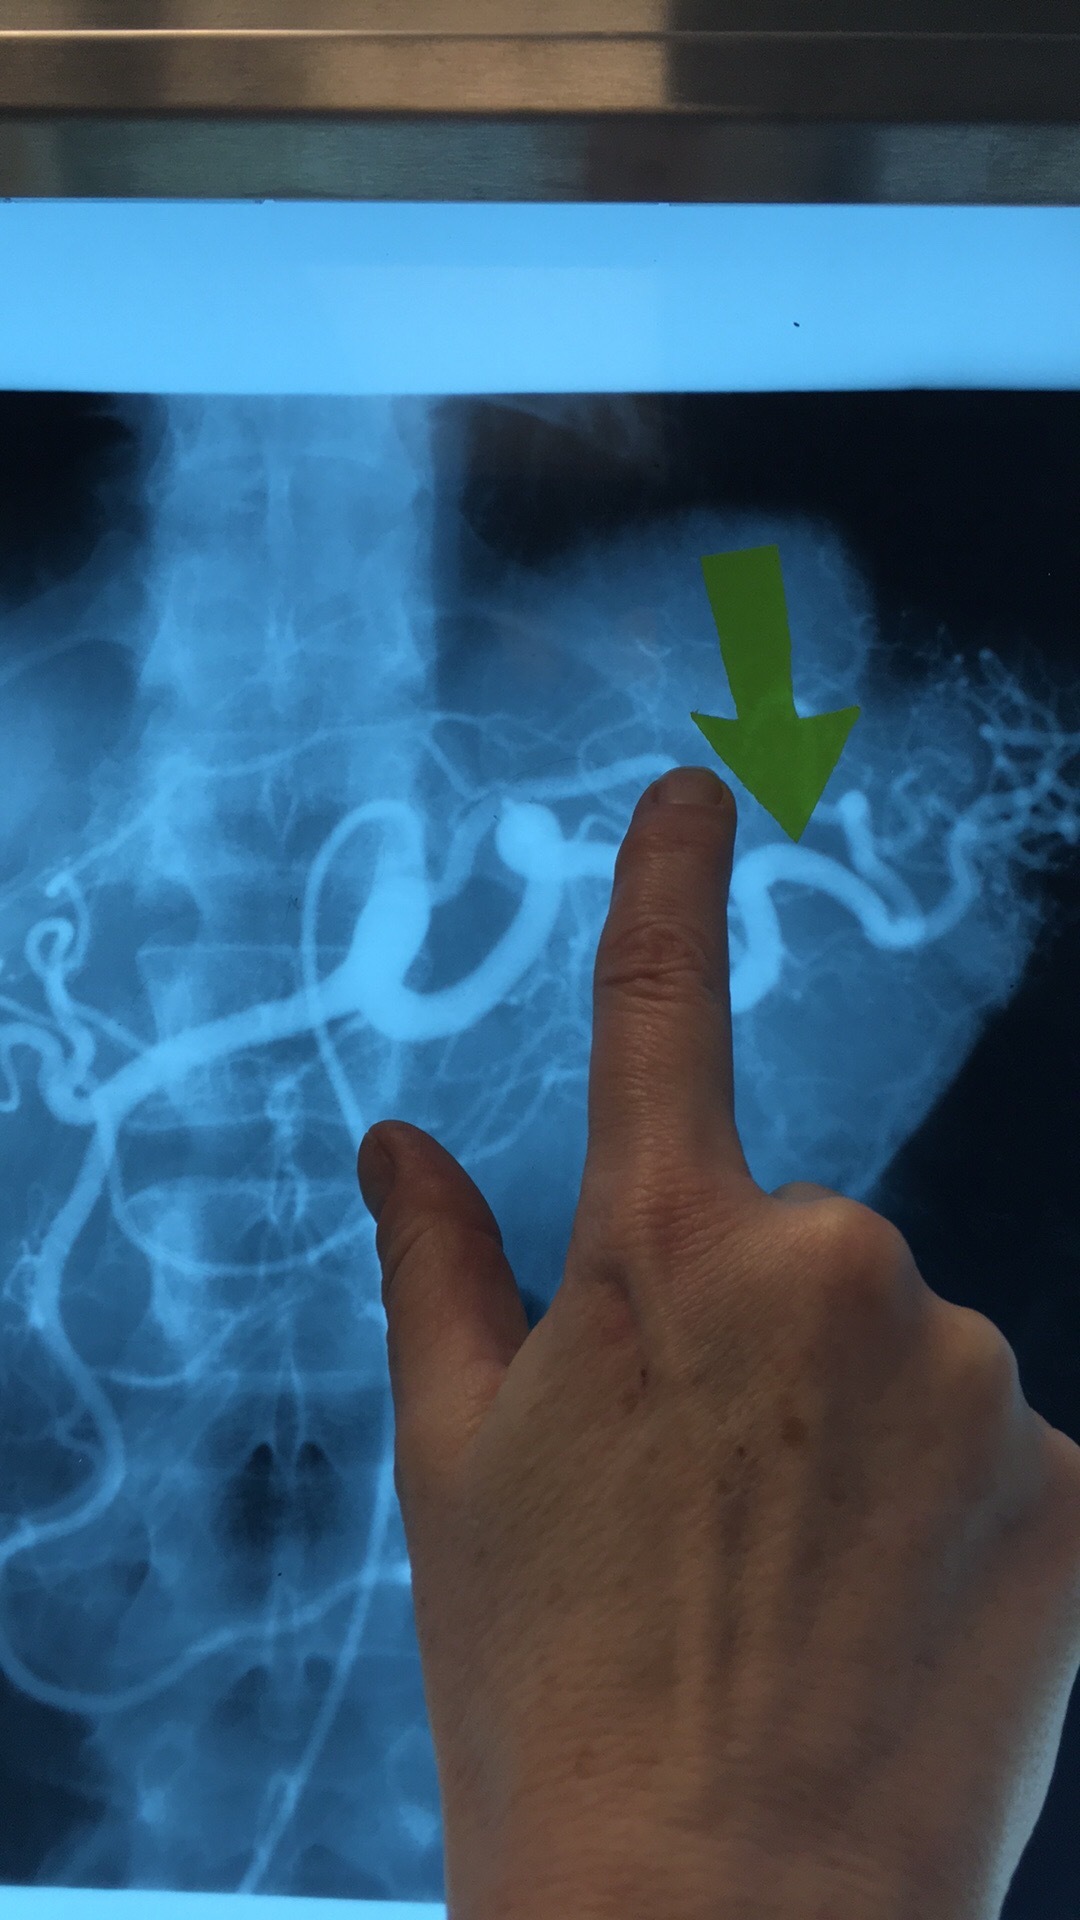

Which artery? What are the 5 branches?

Superior Mesenteric Artery. Intestinal Arteries, Right Colic Art, Middle Colic Art, Ileocolic Art, Inferior Pancreaticoduodenal Art